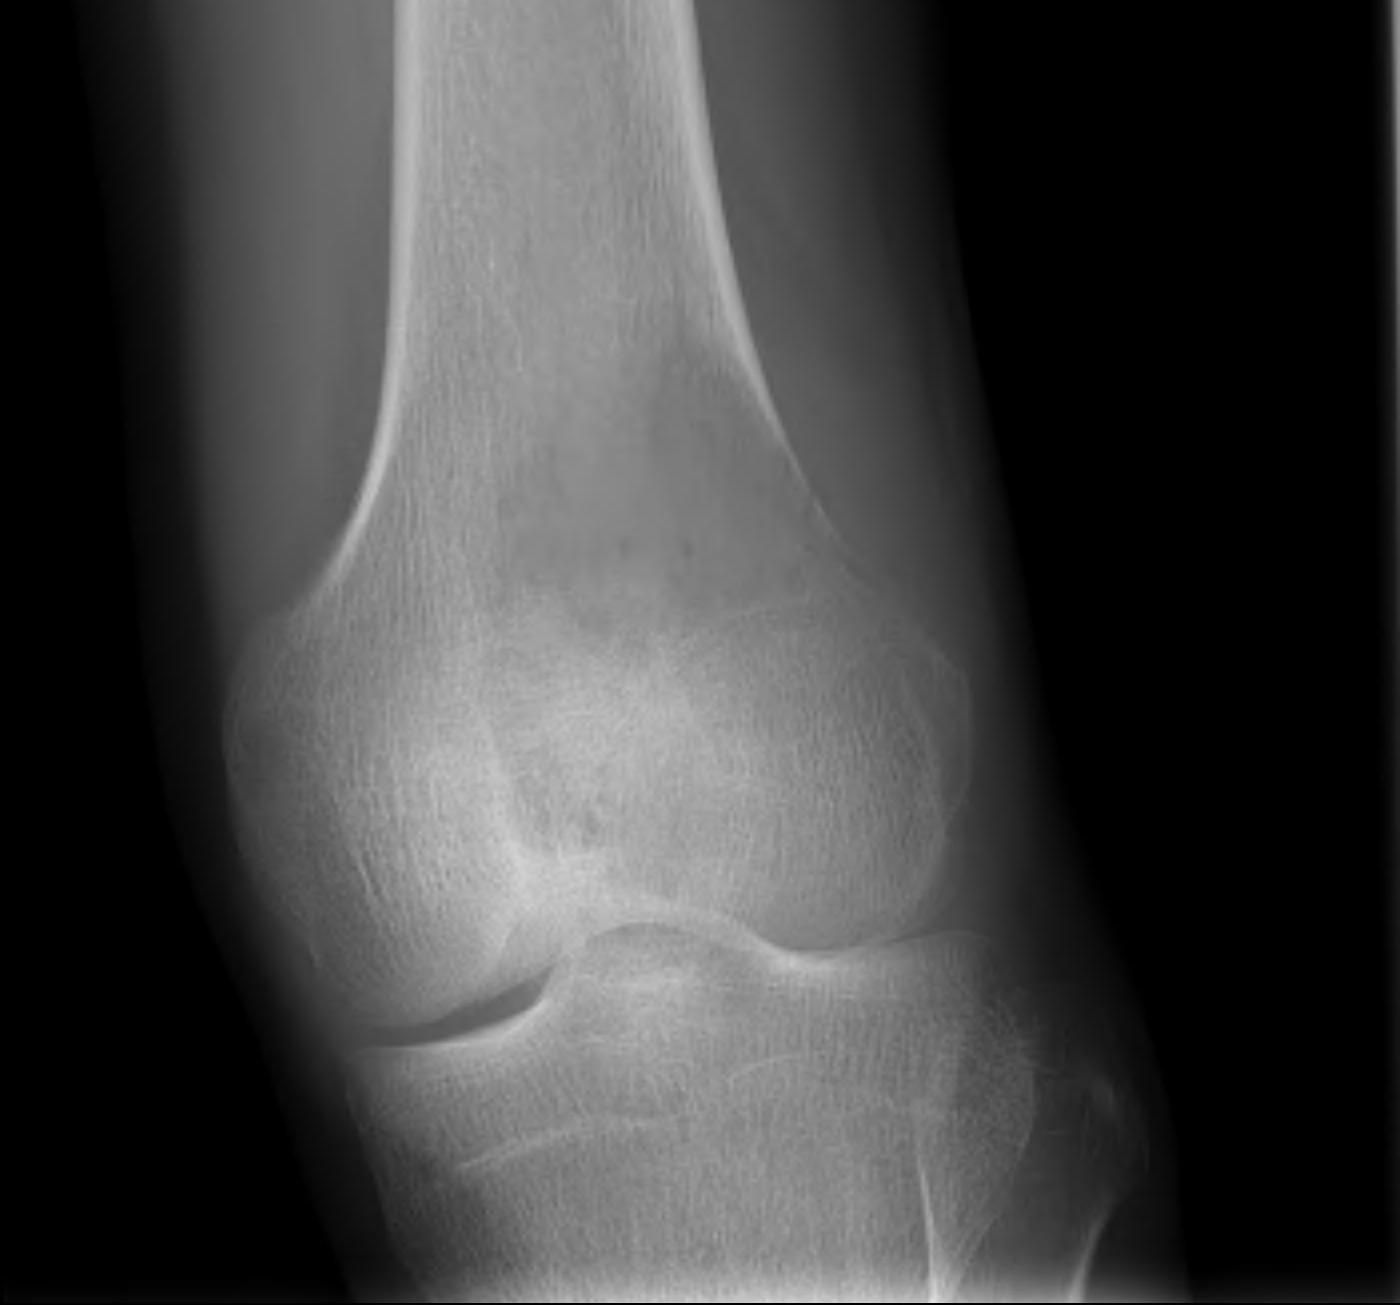

3. Condyles

- medial: incision through vastus medialis

- lateral: anterior to vastus lateralis